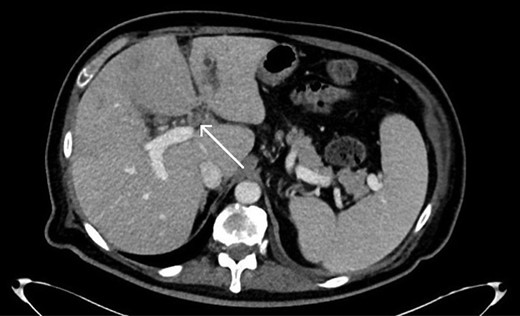

Abdominal imaging findings: axial computed tomography (CT) scan showing the intrahepatic dilation of the left sided biliary system (arrow) from cranial (A) to caudal (B), diffusely thickened gallbladder wall (C, arrow) and left intrahepatic abscess (D, arrow).

Repeat CT imaging revealed continued thrombosis of the left portal vein and anterior branches of the right portal vein and right hepatic artery (Fig. 3). Due to persistent left intrahepatic abscess and concern for an underlying obstructive process in the left biliary system, the patient underwent an endoscopic retrograde cholangiopancreatography (ERCP) which revealed choledocholithiasis which was removed followed by sphincterotomy and stent placement. He subsequently underwent a spyglass™ procedure which noted a left biliary tract occlusion secondary to a mass which was biopsied. Pathology, however, was noted to be benign with debris and bile crystalline material and rare fragments of fibrous tissue with biliary-type epithelium.